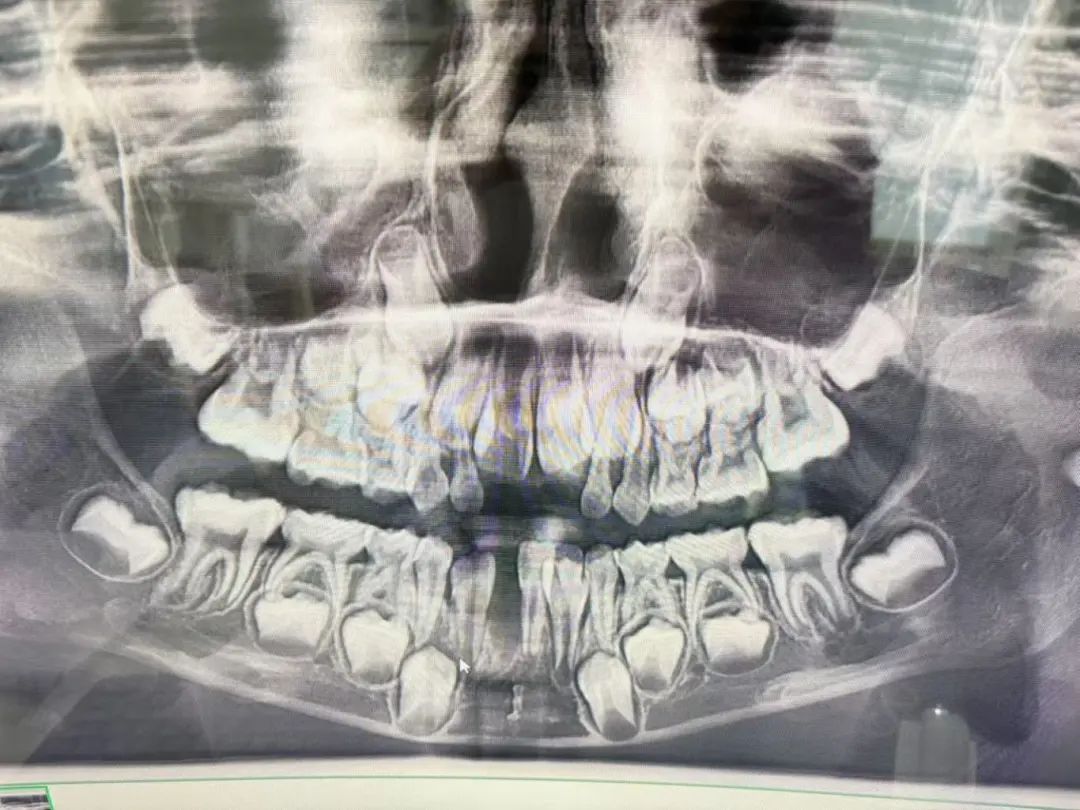

“这颗牙很难拔,拔了很长时间,最后医生拿出来的牙齿是很长的一颗,为此,我觉得很奇怪。孩子告诉我,拔牙后很疼。”孟女士说,医生随后带着孩子去照了一个片,并告诉她,孩子天生缺失恒牙,对此她也不太懂。

孟女士说本来孩子要拔的是右边牙齿,结果医生却把中间的恒牙拔了。

记者从孟女士提供的两张照片上看到,第一张照片上的牙齿是完整的,第二张照片上则有一颗牙不见了,而应该拔掉的那颗牙还在。